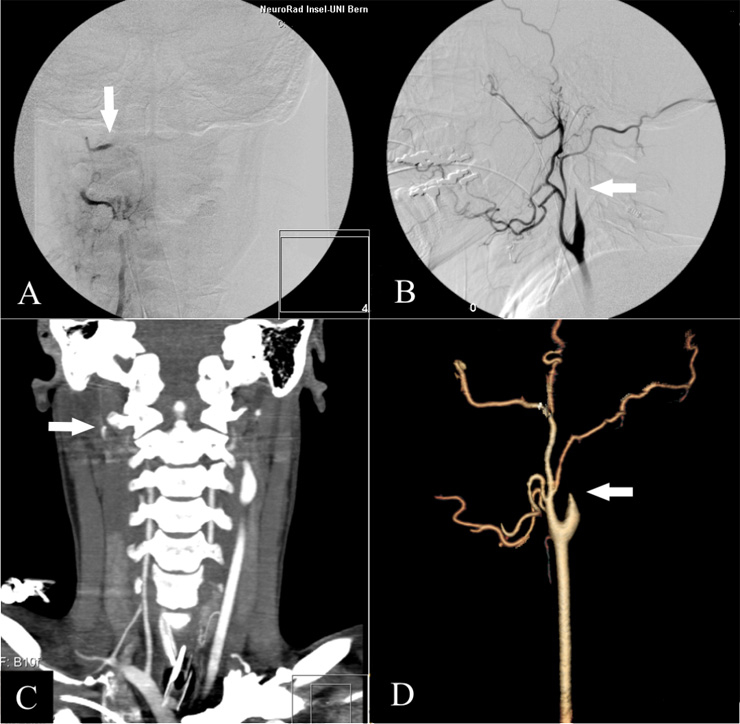

Figure 1

“Gold Standard” DSA: AP view of the right vertebral artery (A) and lateral view of the right carotid artery (B). The stop of contrast in the intersection between extra- and intradural segment of the vertebral artery and the cervical segment of the internal carotid artery are typical angiographic findings (white arrows); in DSA, they are rated as proof of cerebral circulatory arrest.

From the axial CT-Dataset similar views as DSA can be obtained in 2D- (C; vertebral artery) or 3D-reformations (D; carotid artery). For the evaluation of brain death we only use the axial source images. Doing reformations is time consuming, operator dependent and not established in the literature for the determination of brain death. They are shown here only for exemplary purposes and nicely illustrate the lack of intracranial blood supply.